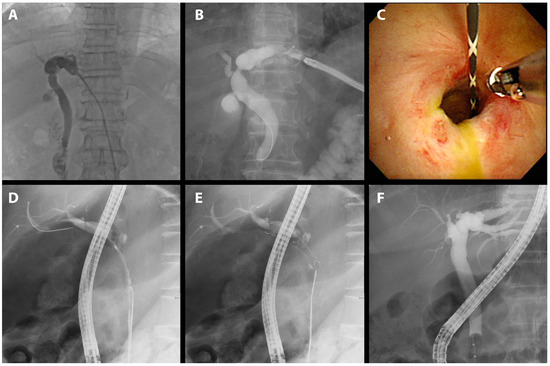

Each endoscopic retrograde cholangiopancreatograph (ERCP) was performed by one of five experienced endoscopists, each with more than five years of experience and more than 1000 successful ERCPs. Throughout the intervention, patients were given a sedative regimen comprising propofol, midazolam, and pethidine while being continuously monitored either by an anesthesiologist or the performing endoscopist. The procedure was performed using duodenoscopes (TJF-260 and TJF-290V; Olympus Medical Systems Corp., Tokyo, Japan) equipped with a 4.2 mm instrument channel, ensuring precise diagnosis and therapeutic intervention. After bile duct cannulation, a guide wire was inserted through the stricture. The stenosis length and the diameter of the proximally dilated intrahepatic duct, as discerned on the cholangiogram, informed the choice of stent dimension, ensuring comprehensive coverage of the stenotic segment (Figure 2A). The placement of the stent was carefully adjusted to ensure the alignment of its central radiopaque marker with the site of the stenosis (Figure 2B). In cases of severe stenosis that hindered catheter insertion, either a balloon dilator (6 mm or 8 mm, Hurricane RX; Boston Scientific, Marlborough, MA, USA) or a bougie dilator (Soehendra Biliary Dilation Catheter; Cook Medical, Bloomington, IN, USA) was used as a preliminary intervention. The stent body was placed inside the bile duct, and the retrieval string was pulled out of the papilla and positioned in the duodenum. Each short FCSEMS was retained for 3 months before being meticulously extracted using endoscopic forceps. Then, cholangiography was undertaken to verify rectification of the BBS (Figure 2D). To ward off potential infections, prophylactic antibiotics were judiciously administered both pre- and post-procedure.

Figure 2.

FCSEMS treatment of biliary anastomotic stricture after cholecystectomy. A case of biliary anastomotic stricture diagnosed after cholecystectomy and treated with FCSEMSs is presented. (A) A biliary anastomotic stricture that had developed after surgery was observed in the common bile duct on cholangiography. (B) The stent was positioned before deployment such that the central radiopaque marker was aligned with the stenosis. (C) An FCSEMS (6 mm in diameter, 4 cm in length; KAFFES) was deployed at the site of biliary anastomotic stricture. (D) After 9 months of FCSEMS use, including two replacements, the stent was removed, and the procedure was terminated after confirming that the biliary anastomotic stricture had resolved.

We treated 75 patients with BBS using short FCSEMSs. The mean age of the participants was 58.3 years; 55 were male and 20 were female. The most common surgery performed on these patients was cholecystectomy, accounting for 41.3% (31 of 75) of patients. This was followed by DDLT, which accounted for 30.7% (23 of 75) of patients. Liver resection was performed in 20.0% (15 of 75) of patients. The remaining 8.0% (6 of 75) of patients were diagnosed with benign strictures. In this study, we presented procedural images of representative cases by cause. A patient who underwent a therapeutic ERCP procedure for biliary stricture following cholecystectomy, a major cause of BBS independent of LDLT, experienced recovery after 9 months of FCSEMS treatment, including two replacement procedures (Figure 2).

A case manifesting common bile duct (CBD) stricture subsequent to DDLT found resolution after a three-month FCSEMS application (Figure 3).